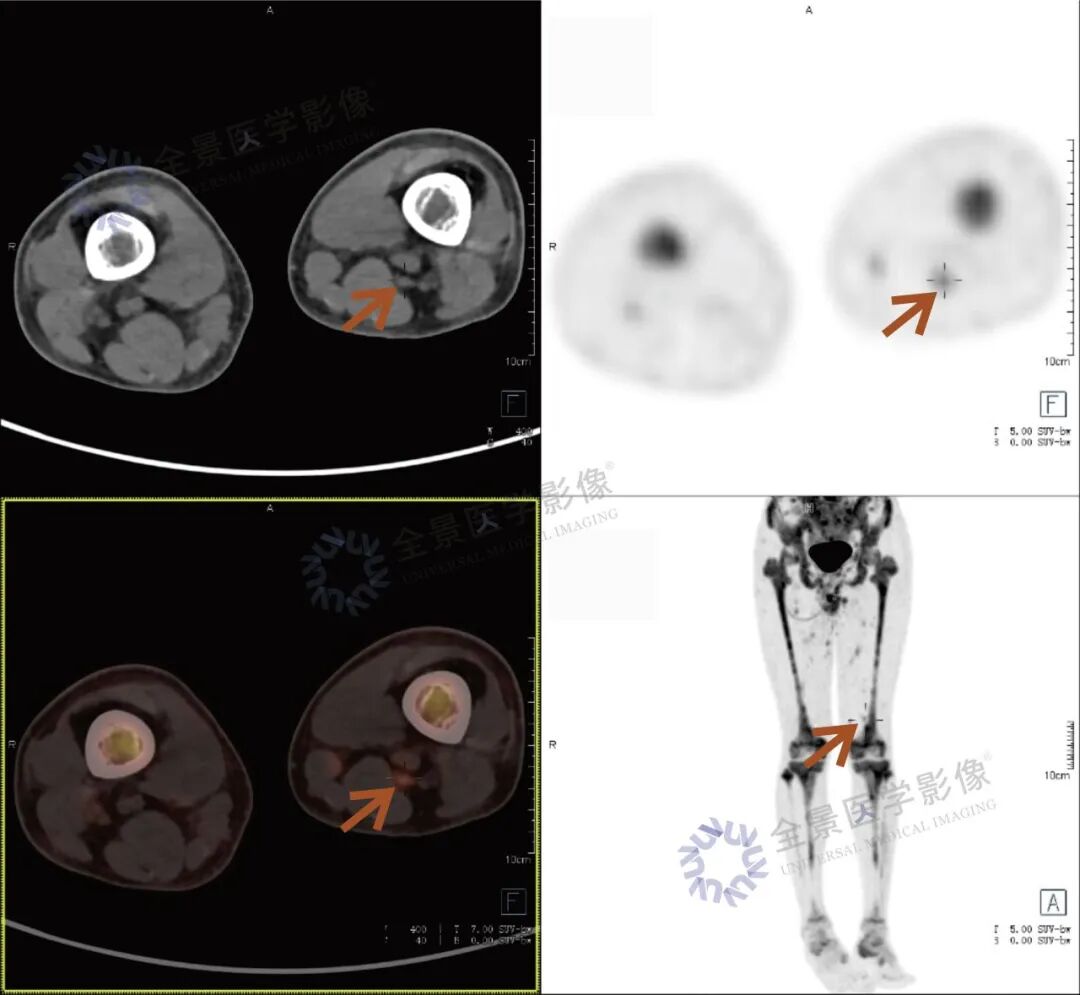

张先生(化名),因持续3个多月的腹痛、腰痛在外院就诊。初始CT检查发现其胸11椎体骨质破坏伴周围软组织肿胀,考虑为“脊柱结核”等感染性病变,并接受了中药治疗。然而,两个月后,张先生又出现了新的症状——牙痛。 经病理活检及免疫组化检查,最终确诊为极为罕见的Erdheim-Chester病。为全面评估这一可累及全身多系统疾病的侵犯范围、明确病灶活动性,并为制定精准治疗方案提供依据,张先生进行了全身PET/CT检查。 PET/CT检查图像: PET/CT检查结果: (1)中轴骨及四肢骨广泛FDG代谢活跃伴信号异常;其中胸10、胸11椎体病灶周围软组织增厚,累及邻近椎管内及双侧椎间孔、双侧胸膜,并与主动脉分界不清。 (2)全身皮下及肌层内多发结节及肿块,FDG代谢活跃;全身软组织广泛肿胀。 (3)鼻咽各壁增厚,顶后壁为著,FDG代谢活跃。 (4)甲状腺多发结节,FDG代谢活跃;双肾及胰腺多发结节及肿块,FDG代谢活跃;双侧阴囊内异常信号伴FDG代谢活跃; (5)左侧锁骨上窝、纵隔内(2L区、3A区)、降主动脉旁、左侧横膈前组、右侧腋窝、左肾周间隙、肠系膜区、双侧髂血管旁多发淋巴结,FDG代谢活跃; (6)心包局部呈结节状稍增厚,FDG代谢轻度活跃; 综上,结合临床,均考虑Erdheim-Chester病所致。 此次PET/CT不仅证实了已知的脊柱病变,更一次性揭示了临床尚未怀疑的、广泛存在于内脏、淋巴结及软组织的隐匿病灶,为疾病分期与治疗提供了决定性依据。